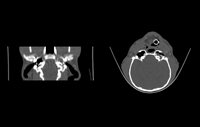

Axial Cuts - Lumbosacral Scanner of a dog - Sagital Reformatting. From the patient's native axial cuts, reconstruction software allows reformatting in all other planes (sagittal, coronal, or oblique). Finally, three-dimensional reconstructions can also be carried out with volume, surface, or endoscopic rendering.

Compared to conventional radiography, the scanner thus allows an overlay of anatomical structures and with a better contrast resolution.